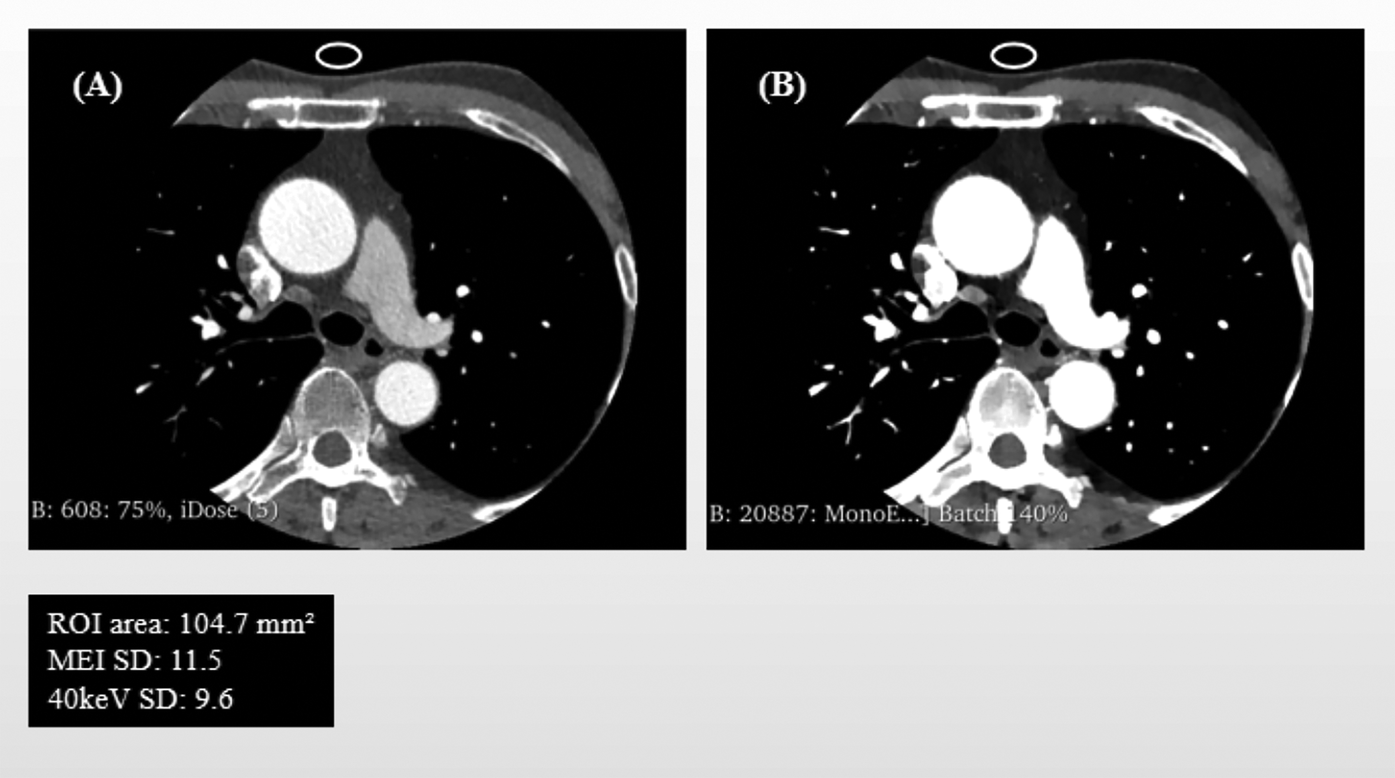

Quantitative analysis was performed using the Segment Statistics module to extract CT attenuation metrics, including mean, median, minimum, maximum, and standard deviation (SD), from the pericoronary adipose tissue region on both images types (Figure 1). Background SD: A ROI of approximately 100 mm2 was placed in an artifact-free area of air outside the patient's anterior chest wall contour within the scan field of view on the MEI, and the same ROI was copied to the corresponding slice of the 40 keV VMI to measure background noise (Figure 2).

Figure 2

Schematic Illustration of Background Noise standard deviation (SD) and ROI Delineation: mixed-energy images (MEI) vs. 40 keV virtual monoenergetic images (VMI). Panel (A) shows the background noise's region of interest (ROI) in MEI, and Panel (B) displays the same ROI copied onto the corresponding 40 keV VMI.